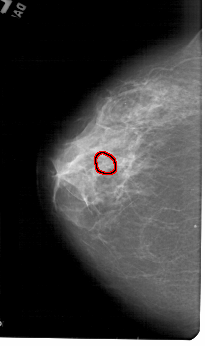

A_1444_1.LEFT_MLO

FILE: A_1444_1.LEFT_MLO.OVERLAY

TOTAL_ABNORMALITIES 1

ABNORMALITY 1

LESION_TYPE CALCIFICATION TYPE AMORPHOUS DISTRIBUTION CLUSTERED

ASSESSMENT 4

SUBTLETY 2

PATHOLOGY BENIGN

TOTAL_OUTLINES 1

BOUNDARY